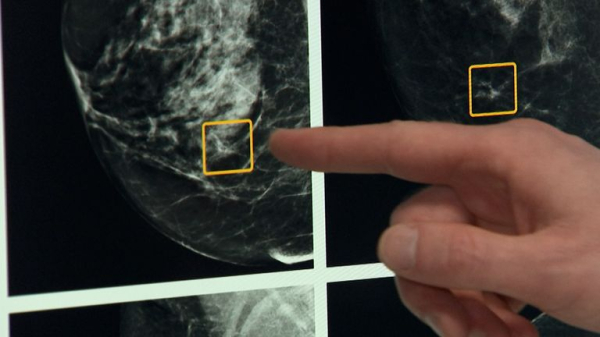

The trial was also the first worldwide study to show that using blood tests to find early signs of cancer resistance to treatment helps patients.

Dr Catherine Elliott, director of research at Cancer Research UK, praised the breakthrough as a “clear example of how blood tests are starting to transform cancer treatment”.

“By tracking tiny traces of tumour DNA in the blood, researchers were able to spot early signs of treatment resistance and switch therapies before cancer had a chance to grow,” she added.

“It shows how circulating tumour DNA, or ctDNA, could help doctors make smarter, more timely treatment decisions.

“This approach could become an important part of how we personalise care for people with advanced breast cancer.”